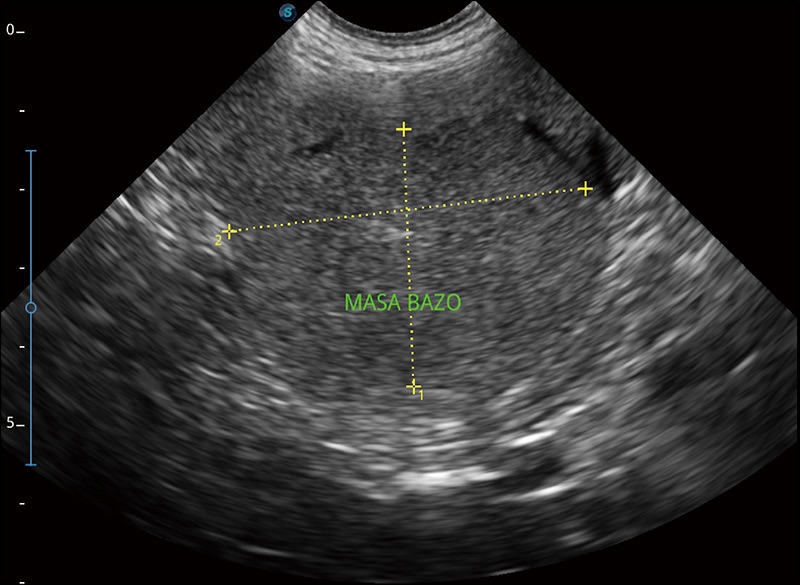

α1卓越的图像质量和便捷的工作流程,使每位宠物医生都能轻松扫查。其全面的兽用应用功能和紧凑型的结构设计,可以满足动物检查的多种需要。专业的预设检查模式和多领域测量软件包有助于为不同类型的动物提供检查, 让宠物医生能够出色的完成工作。

实时宽景成像

可实时观察感兴趣区域和病变位置